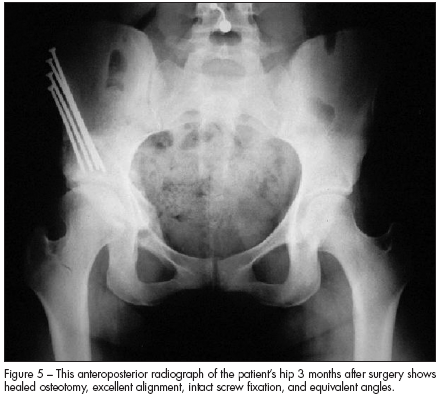

The patient underwent periacetabular osteotomy. She healed uneventfully; Figure 5, an AP radiograph of her pelvis 3 months after surgery, shows the healed osteotomy. At this point, she had very little pain. Her mobility continues to improve, and her risk for early degenerative arthritis is significantly reduced.